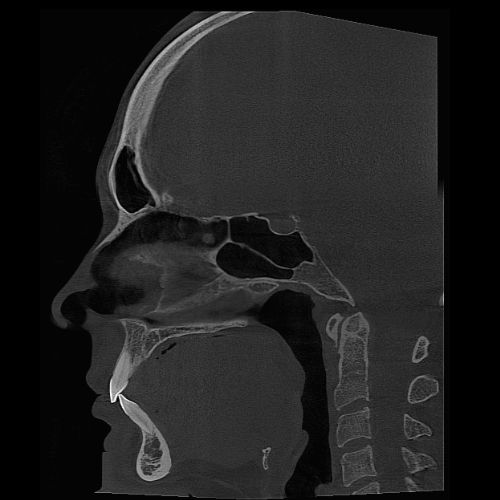

The powerful system components of the PreXion Excelsior Max enable an extraordinary combination of the most precise 3D imaging, large image detail, lowest radiation exposure, reliable diagnostics and digital planning for all indications in modern dentistry, including periodontology, endodontics, implantology, orthodontics, maxillofacial surgery and more. Its patient management system is designed for secure and networked communication of patient data across multiple rooms within a practice and can be integrated into the existing infrastructure with ease.

3D Algorithms: Enhancing Your Work-Flow Efficiency and Diagnostic Accuracy

Patient Motion Correction (PMC)

The PreXion Excelsior MAX algorithm automatically corrects the image imperfections caused by patient micro-movements. This ensures high exam quality, avoiding repetitions and offering greater accuracy for making diagnoses.